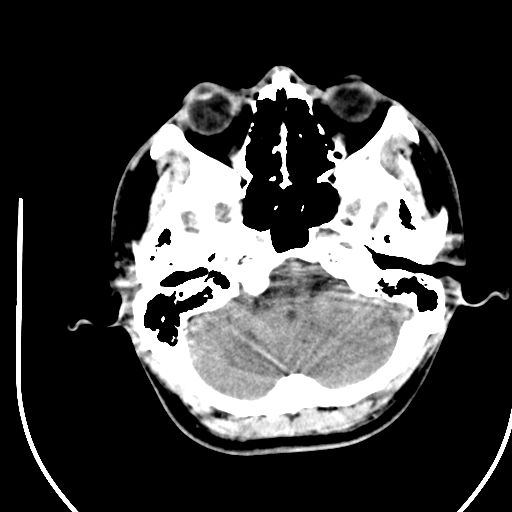

标题: CT28158:男,27Y。头痛数月,左顶叶血管瘤。 [打印本页]

标题: CT28158:男,27Y。头痛数月,左顶叶血管瘤。

考虑avm。

考虑avm。  建议dsa检查。

海绵状血管瘤

考虑左顶叶海绵状血管瘤,建议mr检查。

左侧额叶海绵状血管瘤可能性大;建议行mri检查。

考虑血管畸形,因其周可见水肿,不除外感染性病灶。建议mri检查。